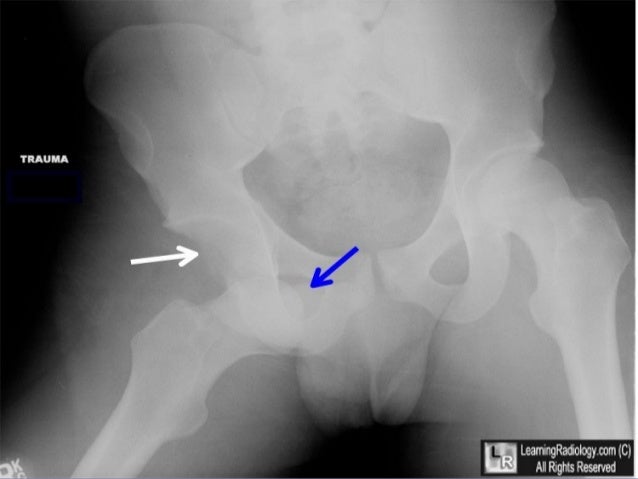

What is dislocation of a prosthetic hip?

Dislocation is when the ball of the new hip implant comes out of the socket. Dislocation is uncommon. The risk for dislocation is greatest in the first few months after surgery while the tissues are healing. If the ball does come out of the socket, your doctor can perform a procedure (called a closed reduction) that can usually put it back into ...

Dislocation is when the ball of the new hip implant comes out of the socket. Dislocation is uncommon. The risk for dislocation is greatest in the first few months after surgery while the tissues are healing.

The most common mechanism of dislocation is impingement. Osteophytes on both the acetabular or femoral side, capsular tissue, or scar tissue can cause a dislocation displacing the head to posterior or anterior. The femur becomes proximalized by the force of the abductors and adductors.

Why would an artificial hip dislocate?